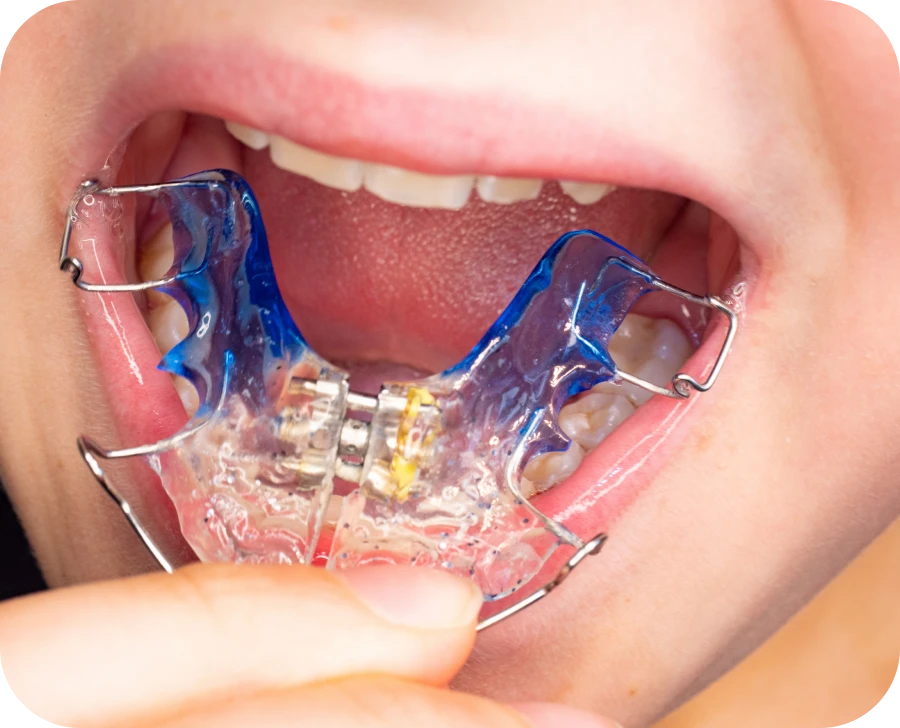

La plaque palatine est un dispositif orthodontique utilisé pour corriger certaines anomalies de la mâchoire et des dents chez l’enfant. Son rôle est d’accompagner la croissance du palais et d’améliorer la position des dents. Cet appareil amovible s’adapte à chaque patient en fonction de ses besoins. Il est souvent recommandé dans le cadre d’un traitement orthodontique précoce pour prévenir des complications futures. Une correction réalisée à temps facilite l’alignement des dents définitives et limite les risques d’interventions plus complexes par la suite.

La plaque palatine repose sur le palais et applique une pression progressive. Cette action modifie la structure osseuse et guide la croissance du palais. Certains modèles possèdent une vis d’expansion qui permet des ajustements réguliers en fonction de l’évolution du traitement. L’activation progressive de cette vis permet d’exercer une force contrôlée sur la mâchoire afin de l’élargir sans provoquer de douleur excessive. Cet appareil favorise aussi une meilleure adaptation des dents en créant plus d’espace pour leur alignement optimal.

Comment se déroule la pose d’une plaque palatine ?

- Prise d’empreinte : l’orthodontiste réalise une empreinte pour concevoir un appareil sur mesure. Cette étape garantit un ajustement optimal.

- Fabrication de l’appareil : la plaque est conçue en laboratoire selon des mesures précises.

- Pose et ajustement : l’orthodontiste installe l’appareil et vérifie son adaptation dans la bouche de l’enfant.